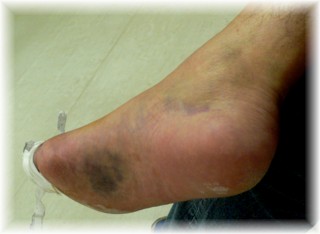

事故当日。

腫れています。外傷はありません。